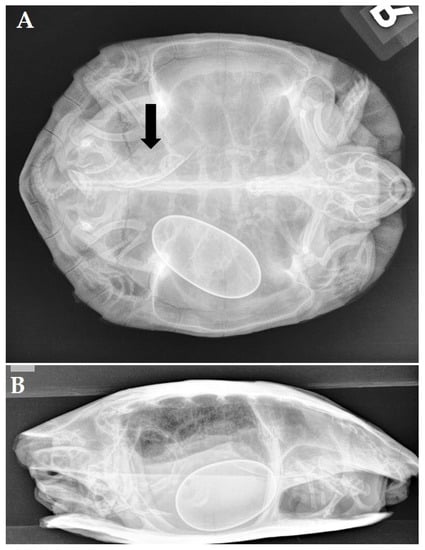

A 19-year-old female yellow-bellied slider (Trachemys scripta scripta) was presented because of anorexia and having displayed overactive behavior for two weeks. During the past 10 years, the turtle had produced two clutches of eggs per year with, on average, 8 eggs per clutch. During the past 5 years, recurrent episodes of dystocia were resolved following the administration of oxytocin by a local vet. Two days before initial presentation, the turtle had received 3 administrations of oxytocin (IM, Oxytocine Kela 10 IU/mL, Kela Veterinaria NV, Antwerpen, Belgium) at 15 IU/kg without effect. An ultrasound revealed the presence of at least 2 oval-shaped eggs, and a radiographic examination (Figure 2A,B) confirmed the presence of 4 eggs with a well-mineralized but thin shell. Three eggs had an abnormal shape, and one egg showed an abnormally small size. The most caudal, large egg showed a vertical position and was located cranial to the pelvis inlet.

Figure 2. Laterolateral (A) and craniocaudal (B) radiograph (horizontal beam) of a yellow-bellied slider (Trachemys scripta scripta) revealing the presence of 4 ectopic eggs with 3 eggs that have a well-mineralized but thin shell and an abnormal shape. The fourth egg has an abnormally small size. The long axis of the most caudal, large egg showed a vertical position and is located in the right caudal coelomic cavity cranial to the pelvis inlet.